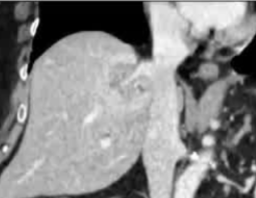

· 单中心、样本量小; 83 岁的女性,体重超标 40 毫米单发 ICC(S7-S8) 中肝静脉和右肝静脉浸润性,活检:非酒精性脂肪性肝炎(慢性肝病),马斯氏(MaS)病(30%)

考虑采用“三步策略 TARE→ PVE → Surgery”方案 剂量活性:1.56 和 3.16 GBq